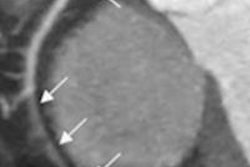

In this scientific session, Duke University researchers will present their software algorithm for automatically segmenting organs in contrast-enhanced abdominal CT scans.Delineation of organs on CT scans is a key component to computer-aided detection, radiotherapy planning, and presurgical planning. However, manual segmentation is often labor-intensive and suffers from intraobserver and interobserver variation, said researcher Qiang Li, PhD.

Automatic and semiautomatic segmentation methods have been proposed, but they remain challenging in comprehensive clinical studies, Li said. As a result, the researchers sought to develop a generic algorithm for segmentation of multiple abdominal organs from contrast-enhanced CT scans.

The team's automated segmentation algorithm was found to greatly improve the efficiency and consistency of organ localization and contouring, according to Li.